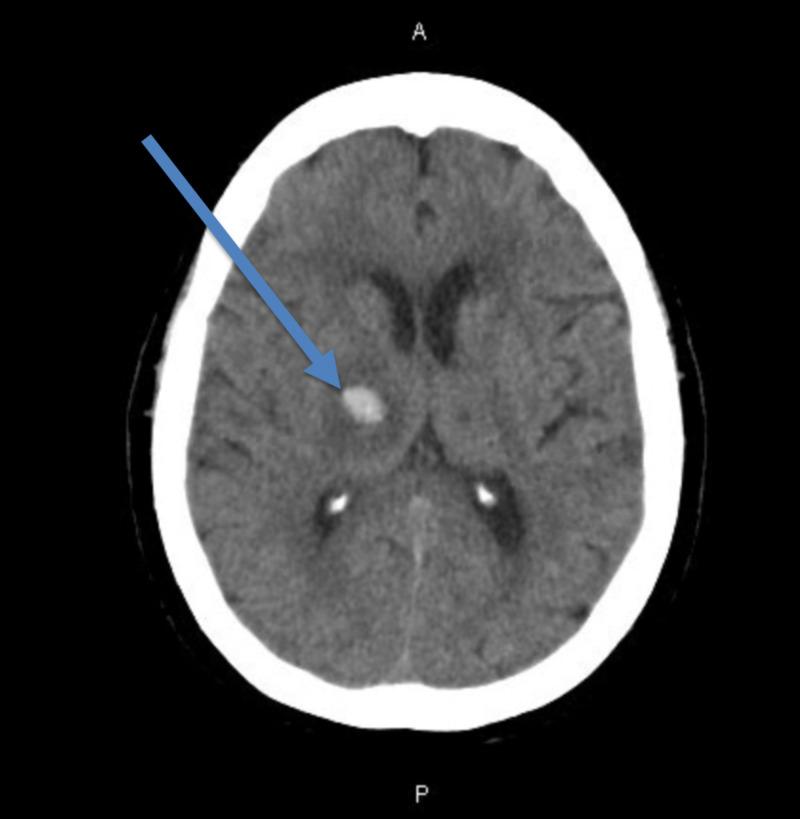

近期颅内出血合并大面积肺栓塞:吸入一氧化氮改善预后的病例报告

Massive Pulmonary Embolism in a Recent Intracranial Hemorrhage: A Case Report of Inhaled Nitric Oxide to Improve Outcomes.

急性大面积肺栓塞(PE)若不治疗,死亡率很高。治疗的主要方法是全身溶栓,但存在一些绝对禁忌证,如颅内出血(ICH)。吸入一氧化氮(iNO)是一种选择性肺血管扩张剂,可降低肺动脉压(PAP),使心脏右心室能以较小阻力泵血。我们报告一例在近期发生ICH的患者中使用iNO改善血流动力学的病例。我们认为这是首例此类报道的病例。一名70岁女性,有服用阿哌沙班治疗PE的病史,最初因身体虚弱就诊,被发现有右侧ICH。因ICH,她出院时被告知停用阿哌沙班,但8天后因严重的心源性休克再次入院,需要血管加压药,且插管后出现难治性低氧性呼吸衰竭。CT显示双侧PE并有右心劳损迹象,遂开始静脉注射肝素。由于她近期有ICH病史,存在绝对禁忌证,禁止使用全身组织型纤溶酶原激活剂(tPA)。介入放射科(IR)会诊确定,鉴于近期的ICH、机械通气以及基于血管加压药需求的血流动力学不稳定,该患者不适合进行导管定向tPA治疗。血管外科和体外膜肺氧合(ECMO)会诊认为该患者无法进行手术。然后该患者开始使用iNO,血压立即得到改善。生命体征一旦稳定,IR会诊进行了肺血管造影并完成了血栓切除术。患者最终拔管,并重新开始服用阿哌沙班。出院16个月后她情况一直良好。对于有全身溶栓禁忌证的大面积PE患者,医生的治疗干预手段非常有限。一些病例报告显示,iNO可改善大面积PE术后患者的全身血流动力学。本病例突出了iNO在有全身溶栓绝对禁忌证的患者中作为潜在辅助治疗手段的可能性。